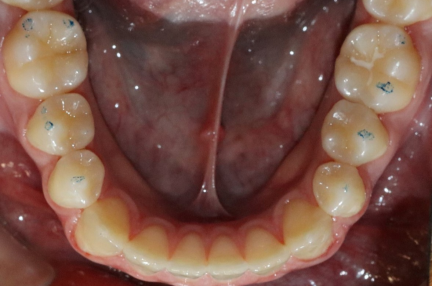

État initial

Classe III, articulé croisé postérieur, articulé croisé antérieur, occlusion bout-à-bout, articulation ouverte, arcades étroites, arcades asymétriques, déviation médiane maxillaire, déviation médiane mandibulaire, décalage médian, chevauchement, rotations

Classe III, articulé croisé postérieur, arcades étroites, arcades asymétriques, déviation de la ligne médiane mandibulaire

Sous-occlusion